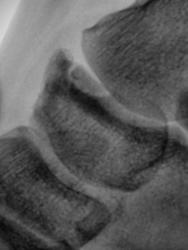

Внутрисуставной оскольчатый перелом основания 5-й плюснеой кости, видел такие пару раз давно, механизм травмы н помню

Да, перелом основания пятой плюсневой кости есть. Линия перелома поперечная, а та, что продольная - это зона роста. А что за фрагмент у верхушки наружной лодыжки? Вероятнее всего старый перелом лодыжки, потому что дополнительных точек окостенения наружная лодыжка не имеет.

Добавочный эпифиз 5 плюсневой кости с эпифизеолизом и переломом основания. В ладьевидной кости добавочная кость tibiale externum. Возле кубовидной кости, вероятнее всего, os cuboideum secundarium

Давайте говорить правильно - апофиз бугристости V плюсневой кости.